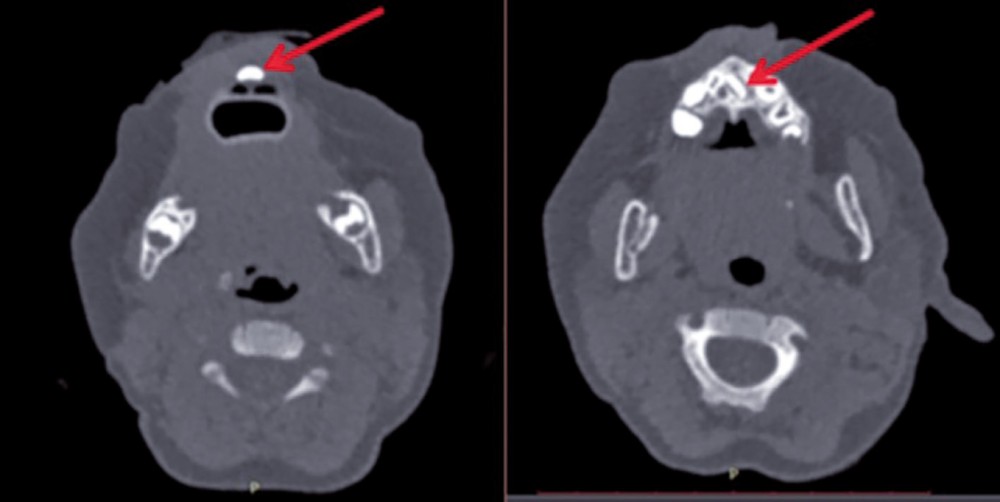

Un scanner, précédemment réalisé à la demande du pédiatre, objective une formation dentaire médiane ainsi que la présence d’un germe unique et médian d’incisive centrale permanente (fig. 3). En outre, il permet d’écarter l’hypothèse d’une fente palatine sous-muqueuse ou d’une sténose des orifices piriformes.